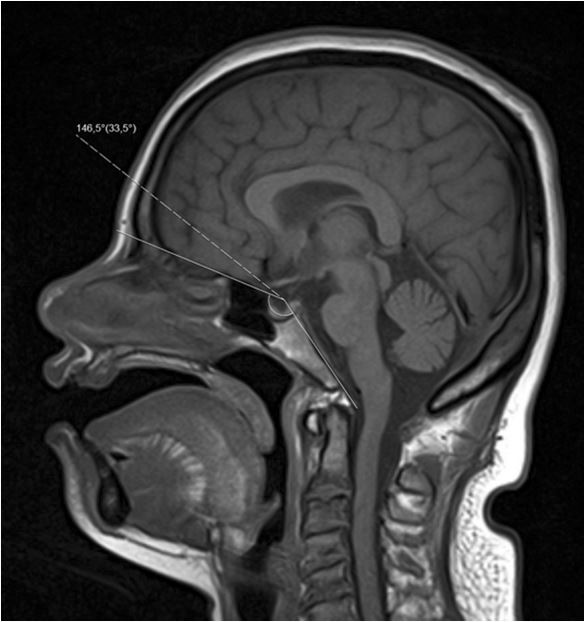

The authors of this paper set out to review and systematize the distinguishing characteristics and abnormalities that can be found in Down syndrome patients. The focus of this study was on the radiological findings in the central nervous system, head and neck, and spine.

Article: Neuroimaging assessment in Down syndrome: a pictorial review